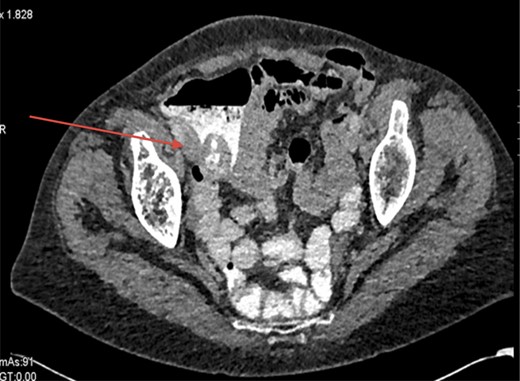

Shown in Fig. 2 is a CT scan showing the caecal mass near to the ileocaecal valve.

CT abdomen was performed showing a 3 cm caecal mass likely submucosal; the histopathology of the biopsy taken on colonoscopy showed only normal colonic mucosa.